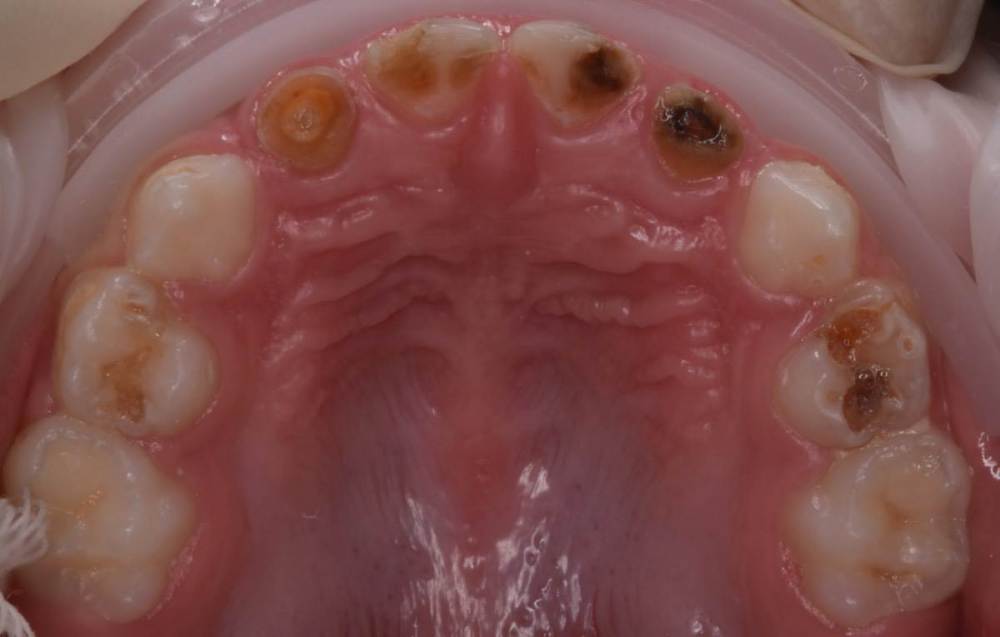

CRAZYDUCK Опубликовано 30 июня, 2022 Автор Поделиться Опубликовано 30 июня, 2022 Пример лечения обратимого пульпита 7.5 зуба . 2 1 Ссылка на комментарий